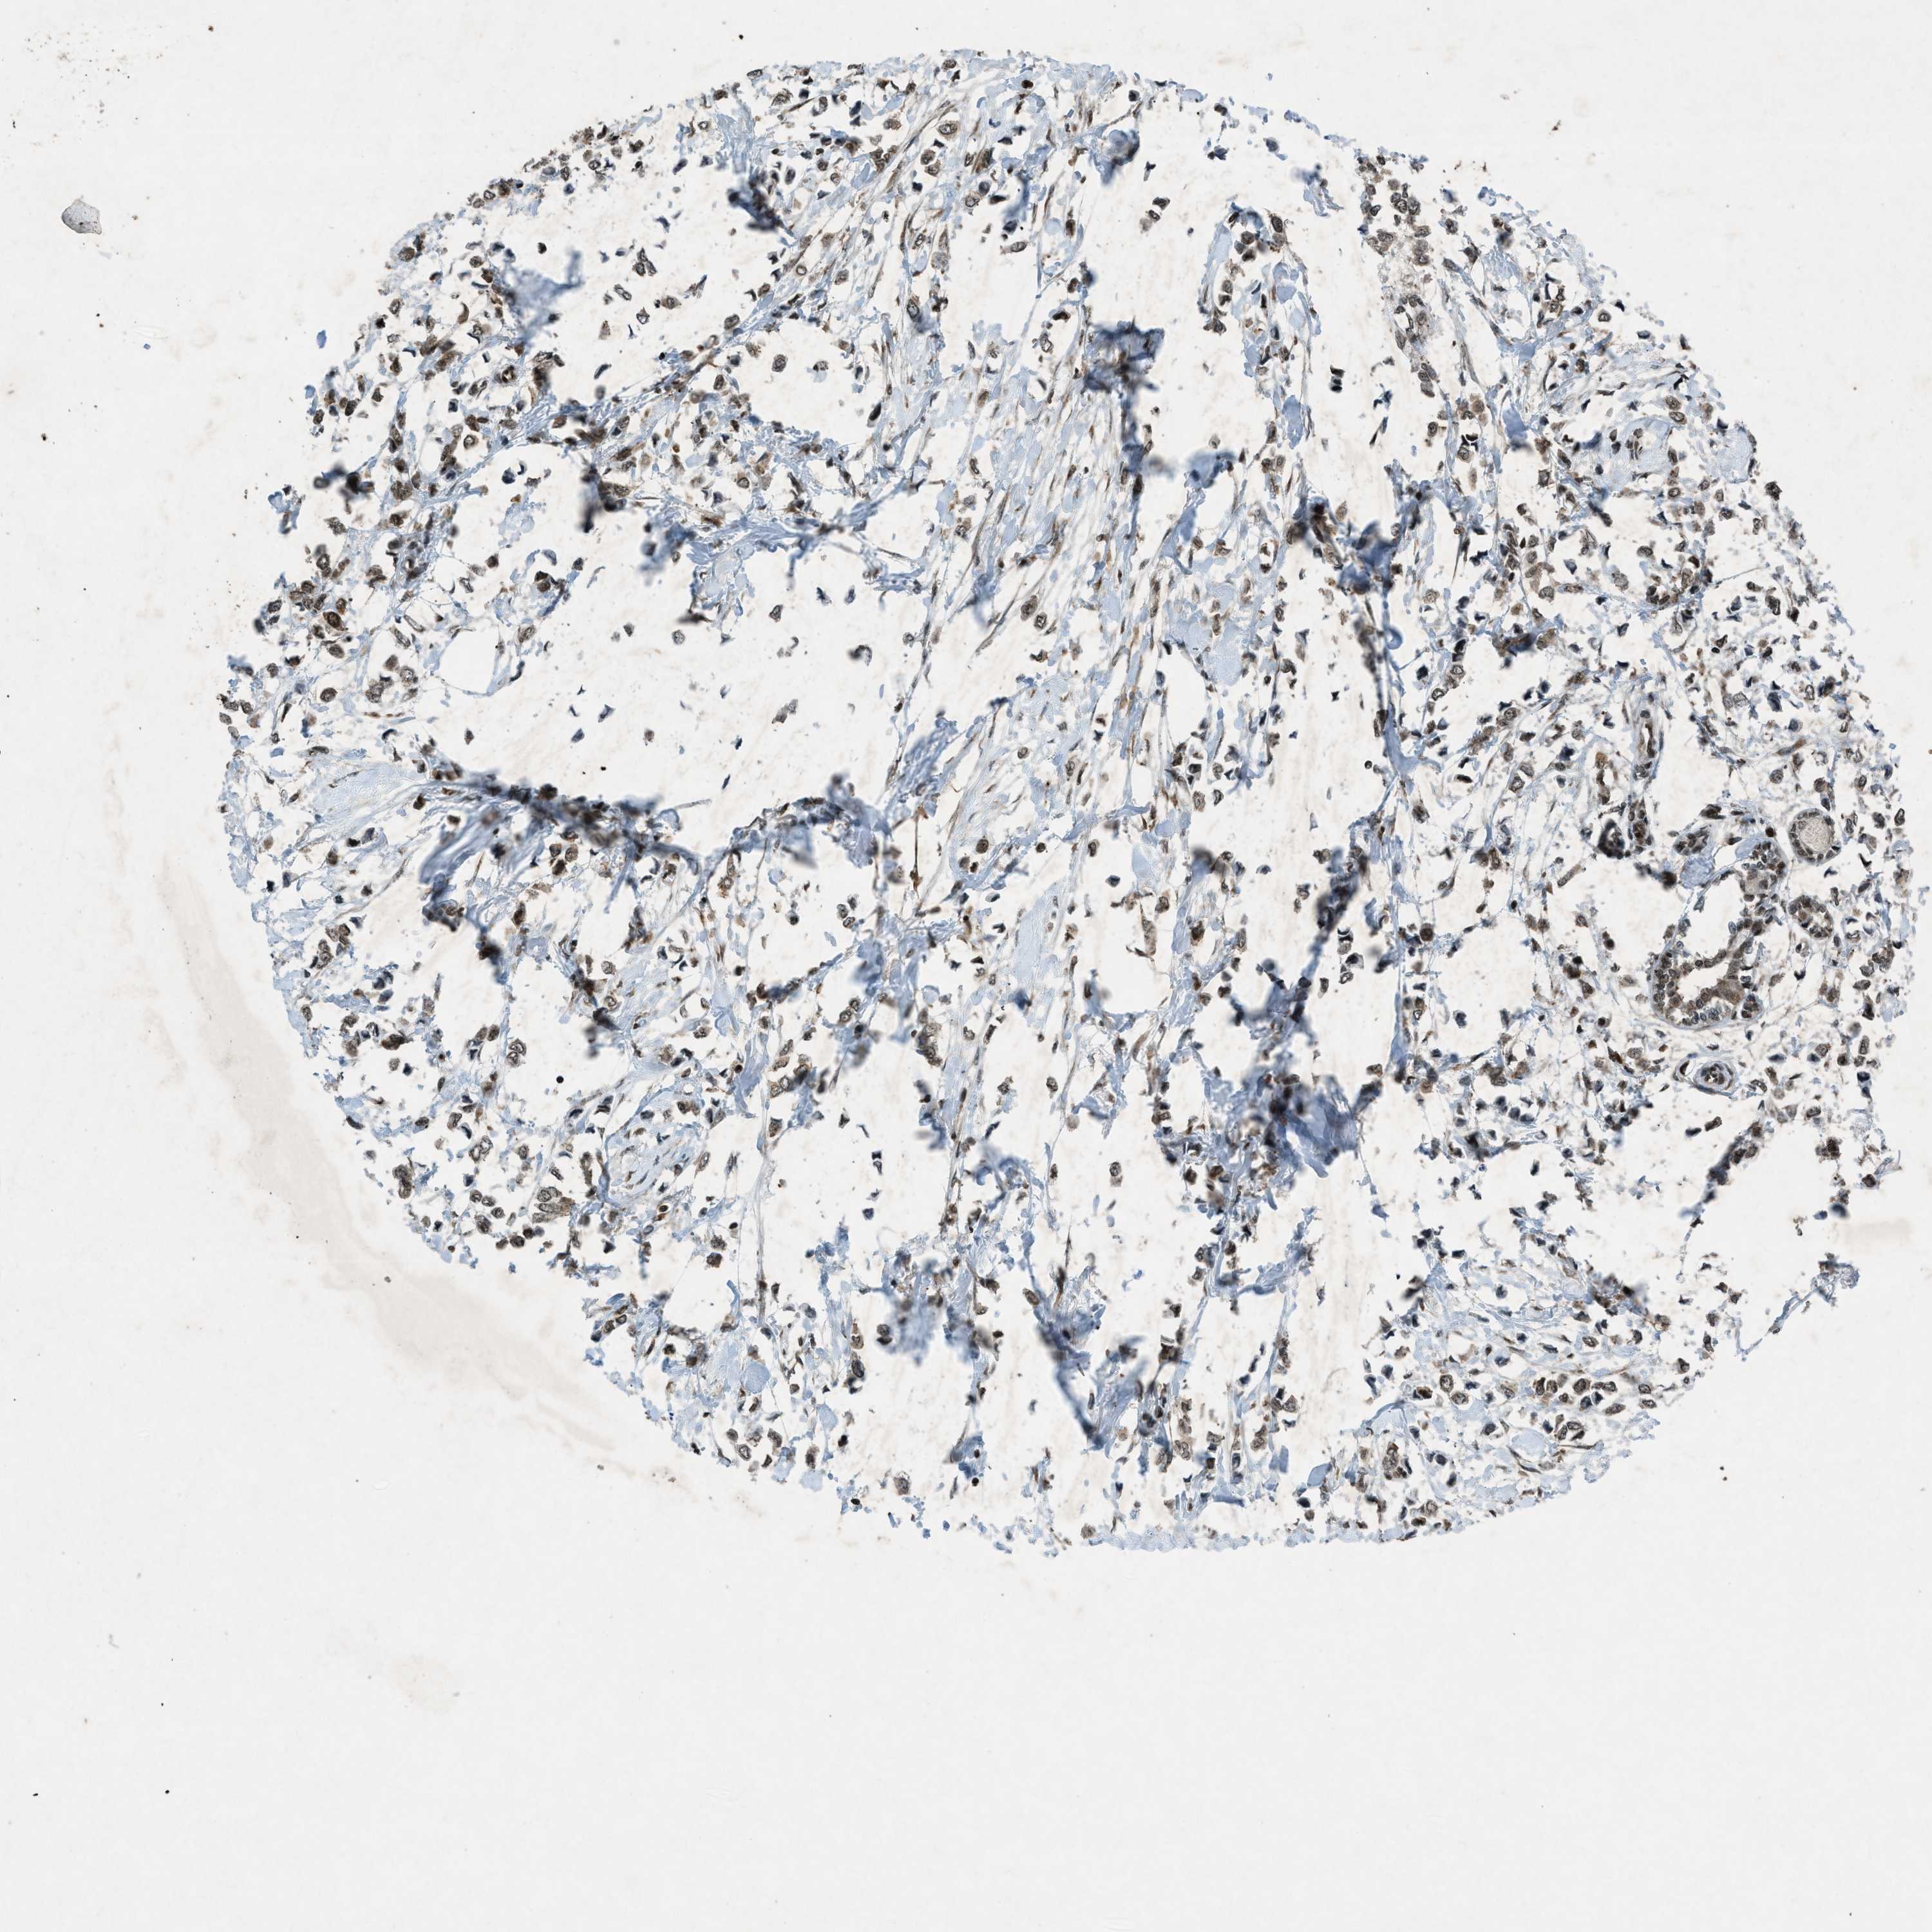

BRCA TCGA BRCA VALIDATION PROTEIN EXPRESSION